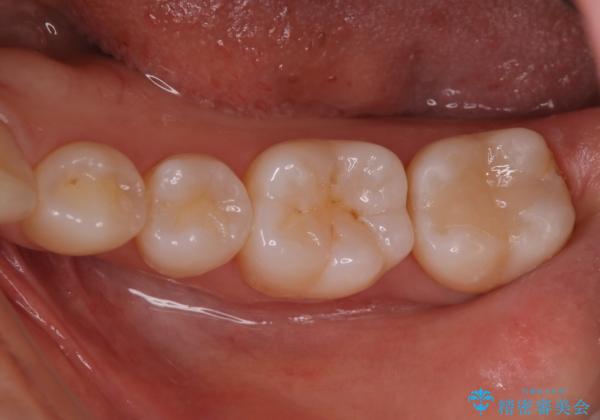

- 銀歯が気になるためやり替えたいとのことで来院されました。

セラミックインレーで治療を行いました。

口の中にチラつく銀歯は適合の良いセラミックインレーでやり替えることで綺麗にやり替えることができます。